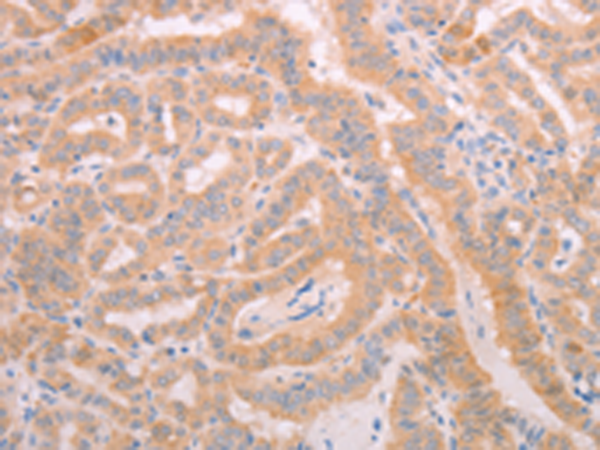

分类: 科研抗体货号: P04531别名: MCH6; APAF3; APAF-3; PPP1R56; ICE-LAP6; CASPASE-9c应用: IHC反应种属: Human, Mouse